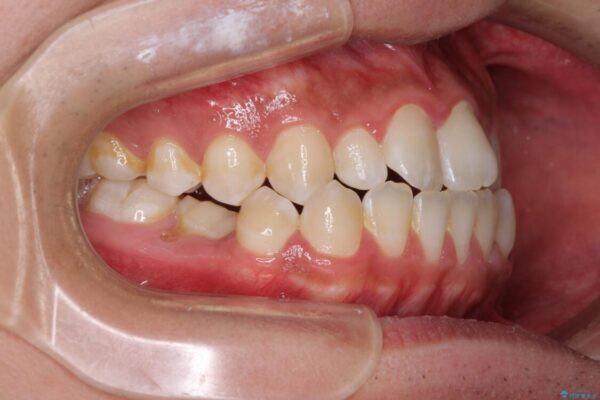

治療前

• 口元の突出感を改善 受け口傾向の咬み合わせの抜歯矯正 治療前画像

受け口傾向の咬み合わせと口元の突出感を気にして来院された患者様です。

受け口傾向特有の狭い上顎歯列であったため、歯列の拡大を補助装置で行い、下顎歯列全体を後方に移動させることとしました。